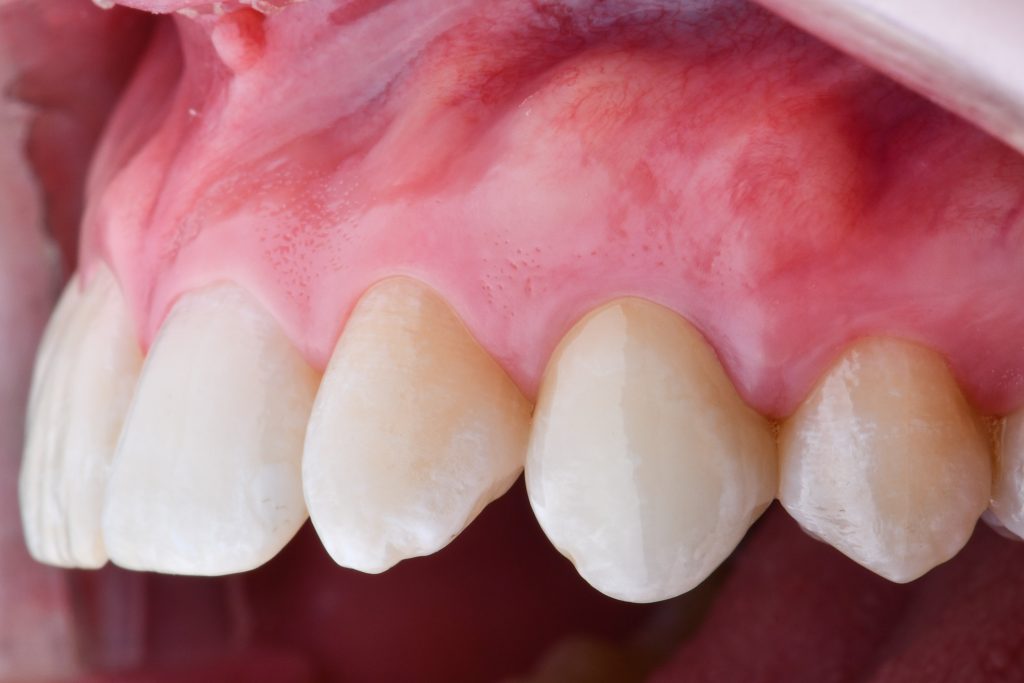

final crown seated, both papilli are fulfilling interproximal areas

the contour of the crest without any collapse

the tooth 23 still in shape of a cuspid